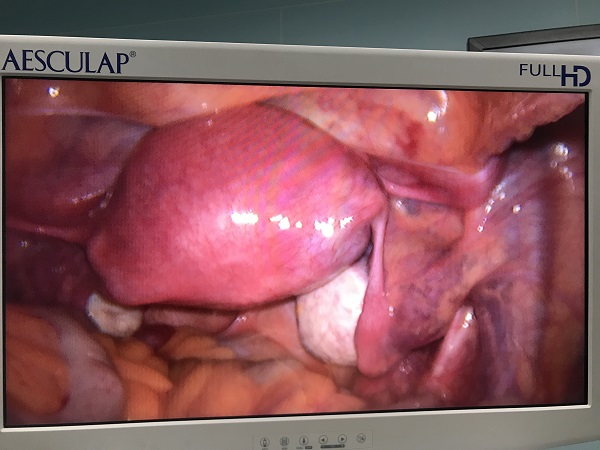

近日,總醫(yī)院婦科團(tuán)隊(duì)成功為一位II型宮角妊娠患者實(shí)施了腹腔鏡監(jiān)測下負(fù)壓吸宮術(shù)。II型宮角妊娠是一種少見的異位妊娠,妊娠囊向?qū)m腔外擴(kuò)展生長使宮角膨脹外凸,一旦破裂可發(fā)生致命的大出血,需于妊娠早期終止妊娠。由于患者強(qiáng)烈要求保留子宮完整,經(jīng)婦科手術(shù)團(tuán)隊(duì)充分討論,在麻醉科和功能檢查科的全力支持配合下,婦科為患者行腹腔鏡監(jiān)護(hù)下負(fù)壓吸宮術(shù)。手術(shù)過程順利,術(shù)后床旁B超顯示宮腔內(nèi)無明顯異常回聲,復(fù)查血液指標(biāo)良好,患者非常滿意。